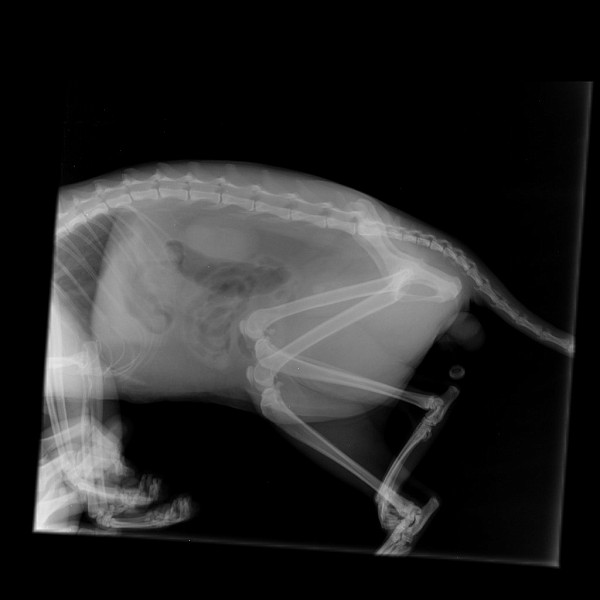

Обработка изображенийВсех кошек с UO следует обследовать с помощью рентгенографии брюшной полости, чтобы исключить мочекаменную болезнь как причину. Важно убедиться, что рентгенограммы охватывают всю мочевыделительную систему, что позволяет выявить мочекаменную болезнь почек, мочеточников, мочевого пузыря и уретры по всей длине.

Свободная жидкость в брюшной полости, на что указывает потеря серозных деталей в каудальном отделе брюшной полости, может наблюдаться, но не всегда вызвана разрывом мочевого пузыря. 8 Повышенная проницаемость мочевого пузыря в результате тяжелого растяжения и диффузного кистозного мурального заболевания может привести к трансмуральному истечению мочи без явного разрыва мочевого пузыря. Уретрография / цистография с положительным контрастом — наиболее чувствительный диагностический тест при разрыве мочевого пузыря или уретры.

В идеале обзорные рентгенограммы должны быть получены до прохождения уретрального катетера, потому что наличие катетера может затруднить обследование уретры, и мочекаменная болезнь может быть не обнаружена. Если пациент находится в критическом состоянии, меры по устранению метаболических нарушений должны иметь приоритет перед рентгенограммами.